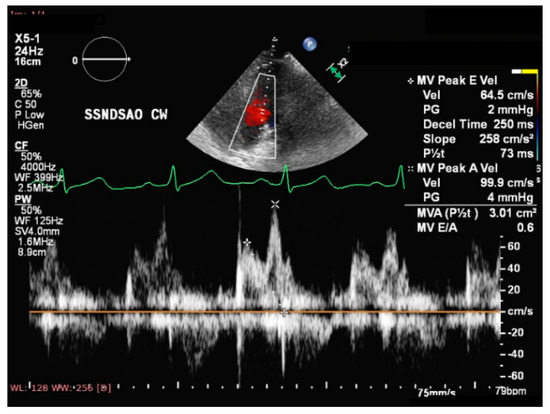

- Esanu, V.; Palii, I.; Mocanu, V.; Vudu, L.; Esanu, V. Left ventricular remodeling patterns in children with metabolic syndrome. One Health Risk Manag. 2020, 1, 41–49. [Google Scholar] [CrossRef]